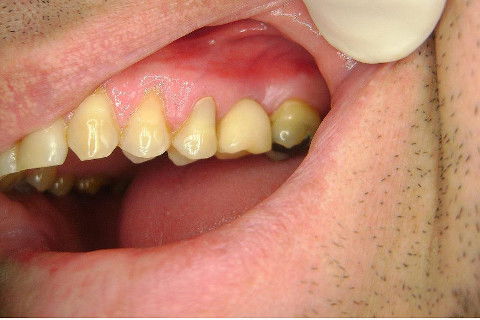

Instalação de um implante em região do 26. Utilizamos um implante cone morse Alvim Neodent 4.3 X 11,5. Foi uma cirurgia muito rápída e minimamente traumática, sem retalho e sutura.